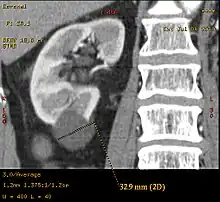

Renal ultrasonography of a simple renal cyst with posterior enhancement.

Renal cyst as seen on abdominal ultrasound

A very small (8 mm) simple renal cyst.

Bosniak II cyst at the lower pole of right kidney with septations within.